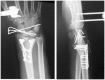

Background: The aim of this study was to compare the functional outcomes and complications of volar and dorsal plating for the management of intra-articular distal radius fractures, with special regard to indications for dorsal plating. Furthermore, we examine the rationale for choosing dorsal plating and its frequency of use.

Methods: Clinical assessments included range of motion measurements at the wrist; grip strength; the Quick Disabilities of the Arm, Shoulder, and Hand score; and the Gartland and Werley score. Clinical results were compared with those achieved using a volarly placed locking plate system. According to Lutsky's plate theory, the rationale for choosing dorsal plating was based on 4 types of pathologic fractures.

Results: Of 112 patients, 38 patients were treated with open reduction internal fixation via a dorsal approach and 68 patients were treated using a volar approach. Except for wrist flexion, there were no other statistical differences in the clinical results between groups for both subjective and objective parameters. There were no statistically significant differences in the complication rates between the volar and dorsal plated groups. One serious complication occurred after volar plating. The most common reason for choosing dorsal plating was irreducible dorsal die-punch fractures.

Conclusions: The treatment of displaced intra-articular distal radius fractures with a dorsally versus a volarly placed interlocking plate system demonstrated similar clinical results. Postoperative complications were not readily observed in the patients treated with a dorsal locking plate. Certain fracture patterns are more appropriately stabilized using a dorsal plate fixation.